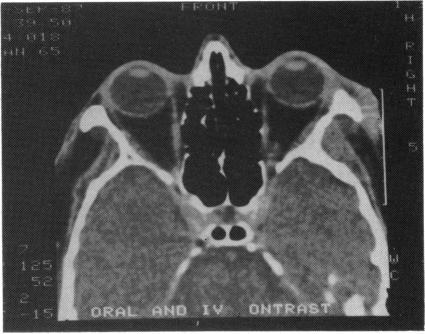

A 61-year-old male presented with a rapidly progressive exophthalmos from small cell lung cancer metastatic to the right orbit. His vision in that eye was 20/200, and his intraocular pressure was 36 mmHg. The orbital metastasis responded dramatically to chemotherapy. One week after starting the chemotherapy the patient did not have exophthalmos, his vision was 20/20, and three weeks later the intraocular pressure was 12 mmHg.